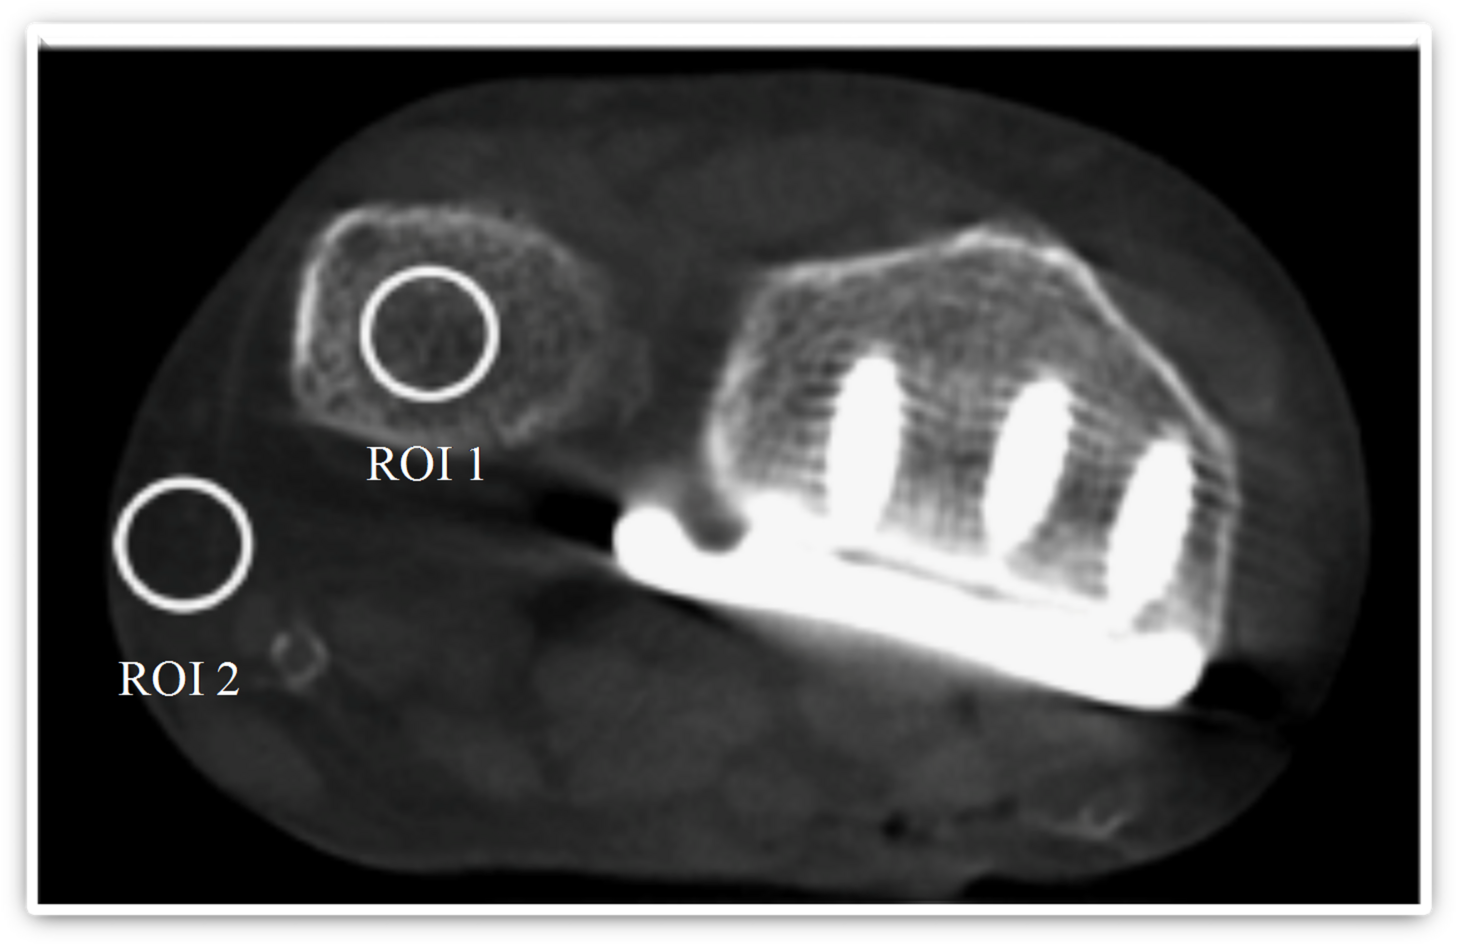

Fig. 3

Representative axial image illustrating standardized regions of interest placed in trabecular bone (ROI 1) and subcutaneous fat (ROI 2) for objective image quality assessment. Regions of interest were defined to calculate signal-to-noise and contrast-to-noise ratios.